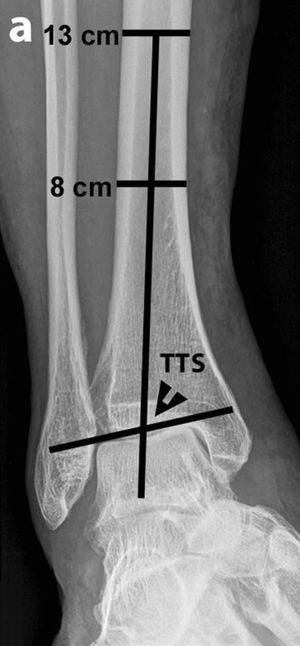

의심되는 내반 또는 외반 변형은 전면 경골거골 표면 각도(TTS)로 측정할 수 있으며, 이는 경골 중앙 종축(경골 천장 위 8cm와 13cm 지점에서 경골을 이등분하는 선 등)과 거골 표면으로 형성된다. 84도 미만의 각도는 ''내반족''으로 간주되며, 94도 이상의 각도는 ''외반족''으로 간주된다.

의심되는 발목 병변에 대한 초기 평가는 일반적으로 투사 방사선 촬영("X-ray")을 통해 이루어진다.[20][21][22]의심되는 내반 또는 외반 변형은 전면 경골거골 표면 각도(TTS)로 측정할 수 있으며, 이는 경골 중앙 종축(경골 천장 위 8cm와 13cm 지점에서 경골을 이등분하는 선 등)과 거골 표면으로 형성된다. 84도 미만의 각도는 ''내반족''으로 간주되며, 94도 이상의 각도는 ''외반족''으로 간주된다.